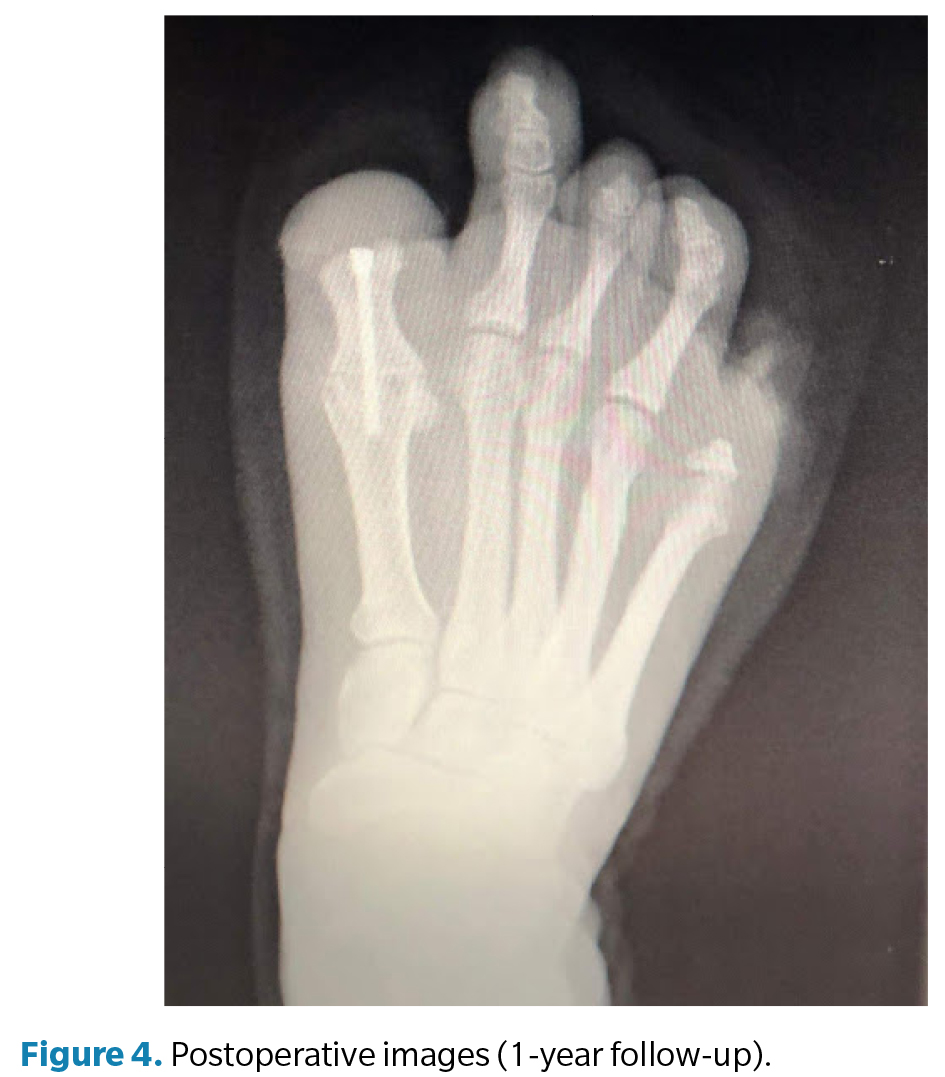

Surgery (Figure 3) was performed in March 2022 under regional anesthesia using a posterior popliteal block and conscdious sedation supervised by an anesthesiologist. Antibiotic prophylaxis with 2 g of IV cefazolin was administered 30 minutes before incision, and a pneumatic ankle tourniquet was applied (250 mm Hg), with controlled pressure and ischemia time limited to 45 minutes. A longitudinal dorsal approach to the first metatarsophalangeal joint was performed, preserving neurovascular structures. Irregular bony remnants of the proximal phalanx were identified and completely resected, followed by contouring of bone margins to achieve smooth, viable surfaces. Articular surfaces of the first metatarsophalangeal joint were then prepared by burring and curettage until an adequate bleeding base for arthrodesis was obtained. Fusion position was determined intraoperatively under load testing, fixing the hallux at approximately 10° dorsiflexion relative to weightbearing surface to optimize propulsion and prevent plantar overload on the residual stump. Final fixation was achieved using one cannulated compression screw, ensuring intraoperative stability and correct alignment under fluoroscopy (Figure 4). The procedure concluded uneventfully, with meticulous hemostasis and layered closure.

The postoperative period included periodic dry dressings and progressive functional follow-up. At 3 months, complete pain resolution and significant improvement in gait quality were observed. At 6 months, the patient showed satisfactory functional recovery, allowing temporary medical discharge. Customized silicone digital prostheses were later fabricated for both feet to improve podiatric symmetry, load distribution, and psychosocial acceptance. At 12-month follow-up, the patient remained asymptomatic, with complete radiographic consolidation of the arthrodesis, correct alignment of the first ray, and stable gait without limitations, confirming the functional success of the procedure.